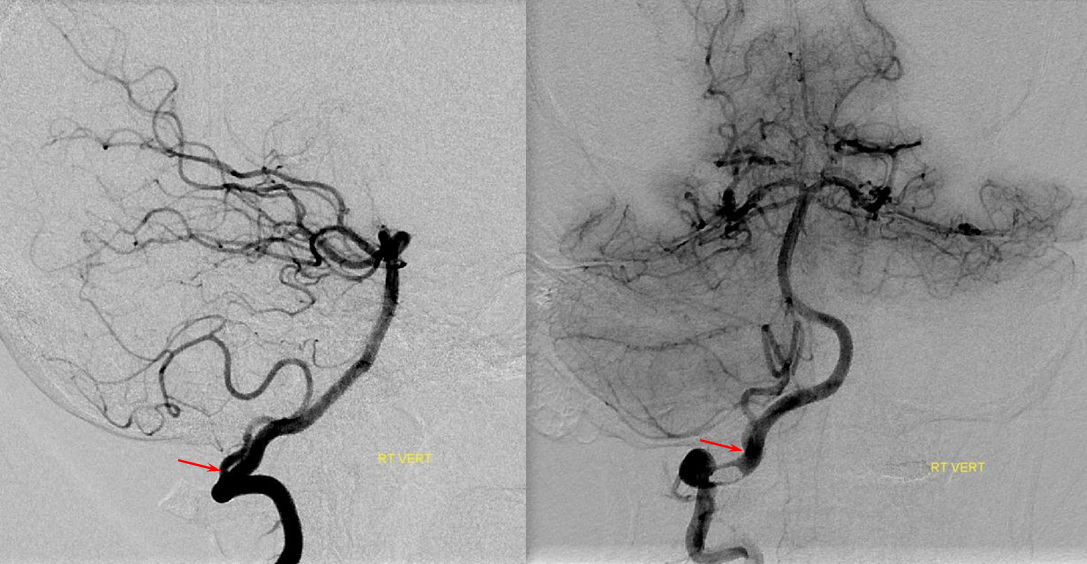

Хирургические процессы при эмболизации гемангиомы на фото

Раздел: Снимки-откровения